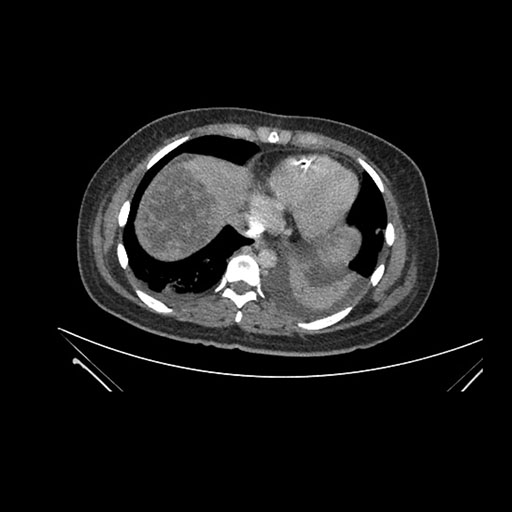

Imaging Analysis

Look through the patient's CT scan to identify any areas of concern for the necessary procedure.

Coronal Arterial

Based on initial findings, which issue(s) would you be most concerned about?